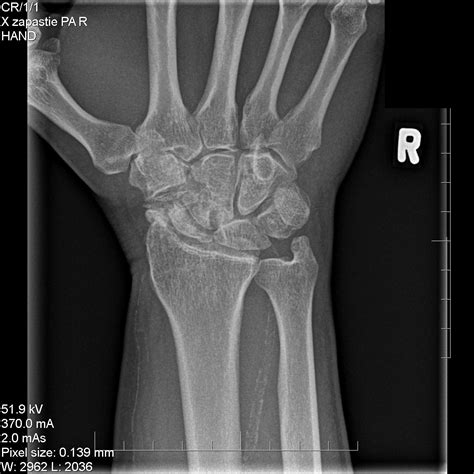

Understand the progression of Scaphoid Nonunion Advanced Collapse (SNAC wrist). Learn about the four stages of this degenerative condition, associated chronic wrist pain, and effective orthopedic treatment options—including surgical interventions and bone grafting—to restore joint function and prevent further carpal collapse. Find expert insights on managing this complex wrist pathology and improving your long-term mobility.